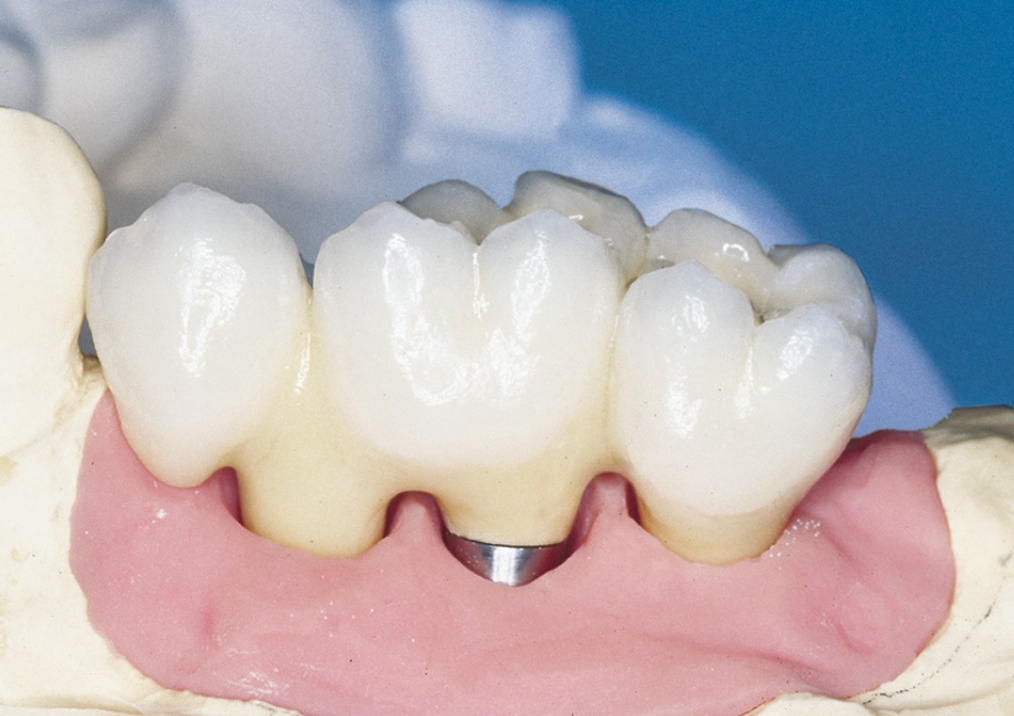

Velká mezera

V případě chybění většího počtu zubů v postranních úsecích čelistí je možné ošetření pomocí implantátů, které nahradí ošetření pomocí snímacích náhrad kotvených na zbývajících zubech nebo patře.

Podmínkou je opět dostatečné množství kosti.

Protetické řešení může být pomocí můstku, který je kotvený na implantátech nebo pomocí jednotlivých korunek na implantátech.

V zásadě je možné do těchto můstků zařadit i přirozené zuby, zejména pokud je potřeba tyto zuby ošetřit proteticky – korunkami. Korunky nebo můstky mohou být na implantáty nacementovány nebo přišroubovány.